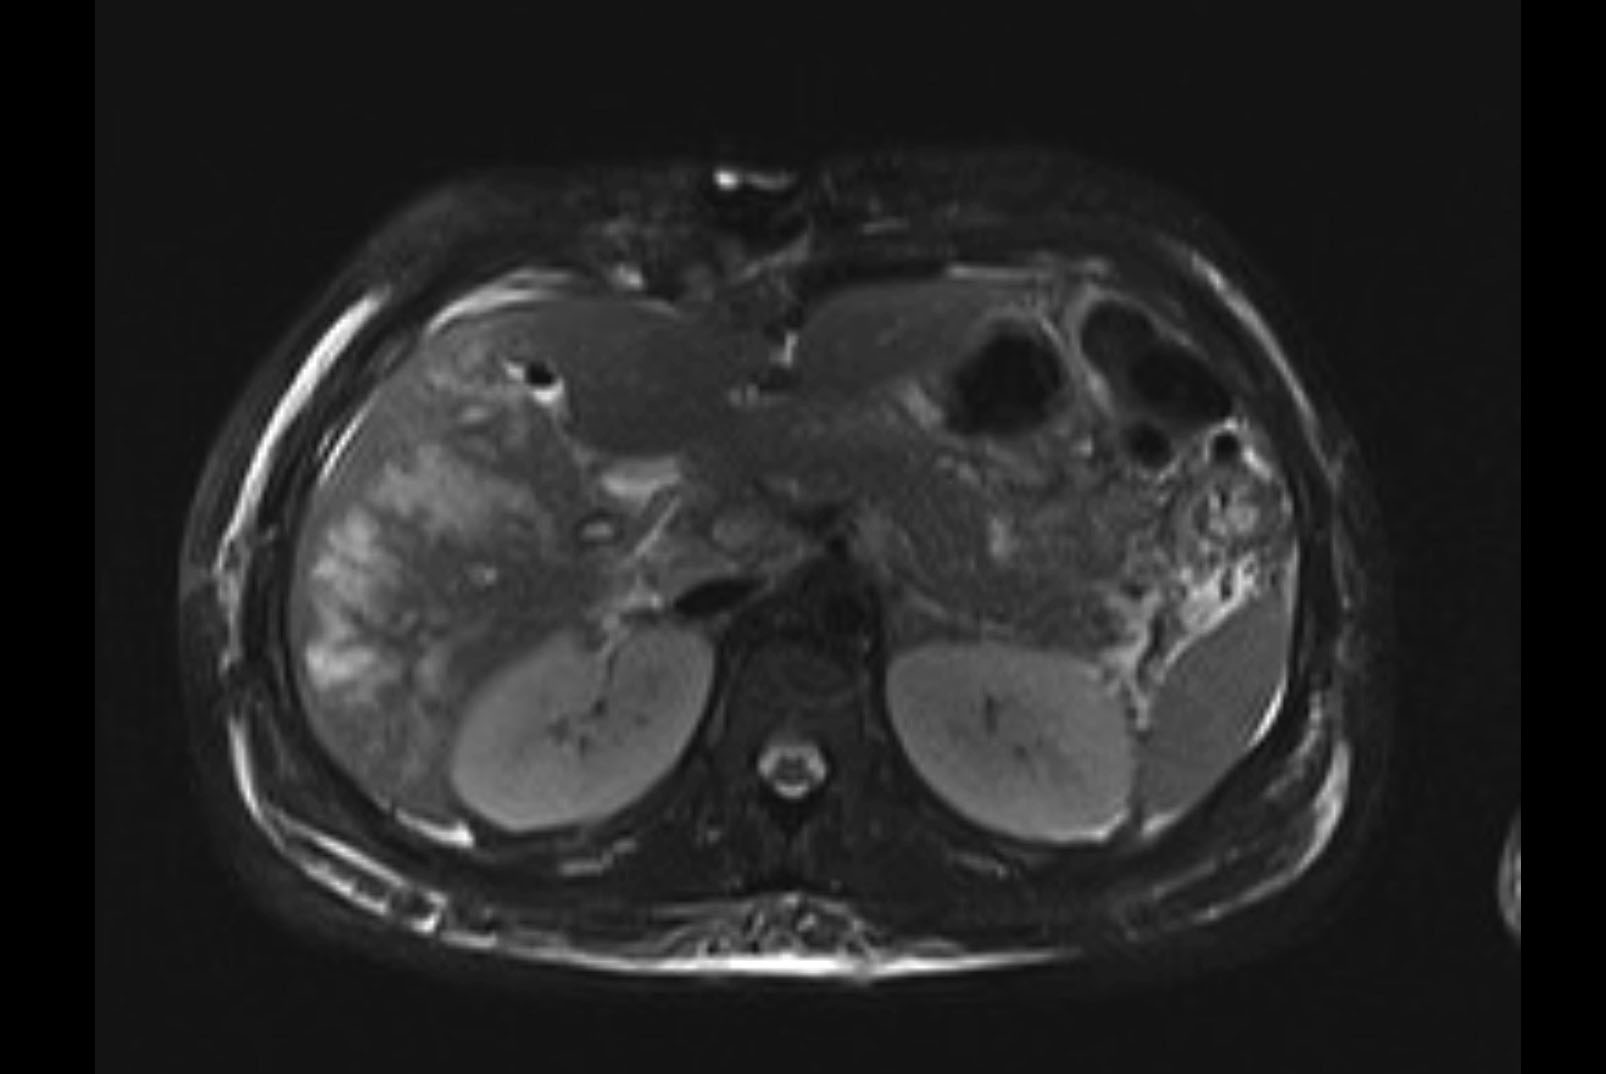

Imaging Analysis

Look through the patient's CT scan to identify any areas of concern for the necessary procedure.

MRI T2

Based on initial findings, which issue(s) would you be most concerned about?